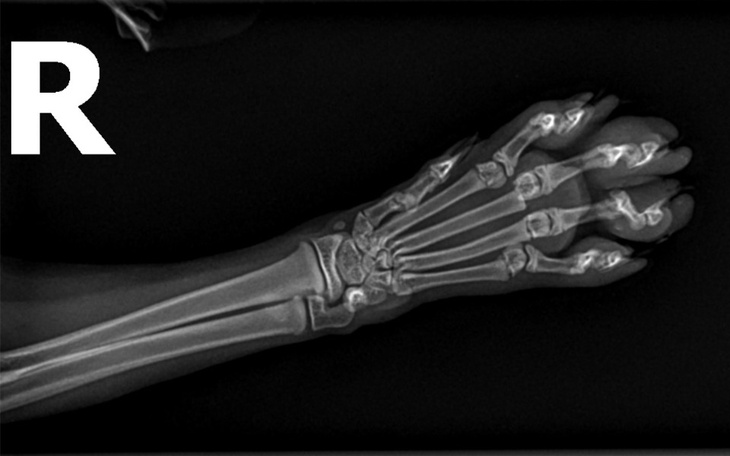

RTG wykazało złamanie dwóch palców. To jednak jest jego najmniejszym zmartwieniem - weterynarz mówi, że nie ma konieczności ingerowania w złamanie, bo nie jest na tyle poważne. Niepokoi natomiast brak czucia w łapie. Dziś mija 7. dzień codziennego podawania leków i zastrzyków i niestety zmian na lepsze nie ma. Opuchlizna lekko zeszła, ale czucia wciąż brak. Na razie nie mamy pewności czy uszkodzenie jest tymczasowe czy trwałe. W najgorszym wypadku trzeba będzie amputować końcówkę łapki...

Poniżej zdjęcia RTG łapki, wypis od weterynarza oraz faktura, która jest jedynie za pierwsze dwie wizyty. Za leki i zastrzyki, które Szymon nadal bierze dostaniemy osobną fakturę.